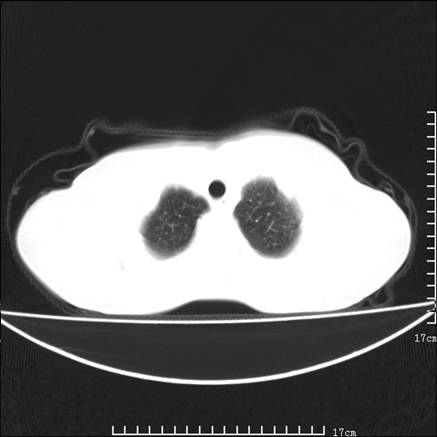

女,46岁,患胃溃疡多年,溃疡大小约1.0cm左右,后于5年前手术,病理为胃癌。主诉:半月前感冒后胸闷,气短,有咳嗽,无明显咳痰,无发热。偶有腰背部不适。

以下为高分辨扫描图像